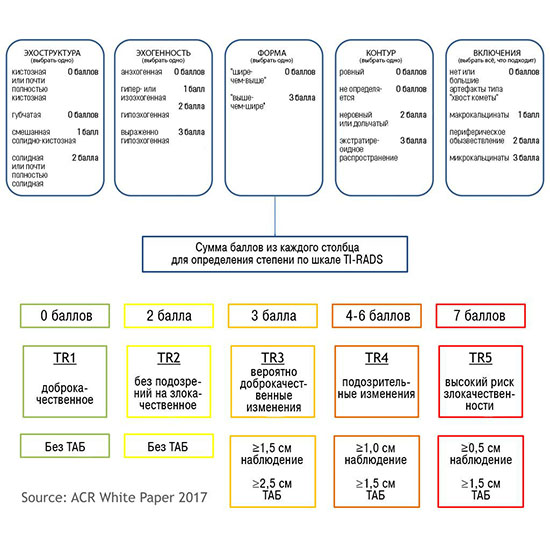

Исследование щитовидной железы одно из самых простых в ультразвуковой диагностике. Подходов к диагностике очень много, и когда они друг другу противоречат необходимо обратиться к международной практике. На сегодняшний день наиболее авторитетное международная организация это American Institute of Ultrasound in Medicine (AIUM). Данной организацией, по вопросам щитовидной железы, утверждены две системы это ACR (American College of Radiology) Ti-RADS и авторская система (С.И. Матящук) ThyrNoDUM.

Суть в том, что достоверно по сонограмме не возможно определить гистологический тип узлового образования, однако мы может определить статистический тип (ThyrNoDUM) и класс риска с показанием к биопсии по скоринговой системе (ACRTi-RADS).

1) Узел занимает всю левую долю, но прорастает капсулу щитовидной железы (0 баллов), больше широкий чем высокий (0 баллов), не имеет кальцинатов (0 баллов), с ровным четким контуром (0 баллов), изоэхогенный (1 балл), тканевой структуры (2 балла). Количество баллов 3, ACRTi-RADS 3, ThyrNoDUMК3. Показана пункция в связи с большим диаметром узла (более 2,5см для Ti-RADS 3)

2) Узел у перешейка, не прорастает капсулу щитовидной железы (0 баллов), больше широкий чем высокий (0 баллов), не имеет кальцинатов (0 баллов), с ровным четким контуром (0 баллов), гипоэхогенный (2 балла), тканевой структуры (2 балла). Количество баллов 4, ACRTi-RADS4, ThyrNoDUMК6. Пункция не показана в связи с малым диаметром узла (более 1,5 см для Ti-RADS4), рекомендовано наблюдение.

3) Узел правой доли, не прорастает капсулу щитовидной железы (0 баллов), больше широкий чем высокий (0 баллов), не имеет кальцинатов (0 баллов), с ровным четким контуром (0 баллов), изоэхогенный (1 балл), смешанной структуры (1 балл). Количество баллов 2, ACRTi-RADS2, ThyrNoDUMК1. Пункция не показана в связи с низким риском.

4) Узел правой доли, не прорастает капсулу щитовидной железы (0 баллов), больше широкий чем высокий (0 баллов), не имеет кальцинатов (0 баллов), с ровным четким контуром (0 баллов), изоэхогенный (1 балл), смешанной структуры (кистозно солидный) (1 балл). Количество баллов 2, ACRTi-RADS2, ThyrNoDUMК1. Пункция не показана в связи с низким риском.